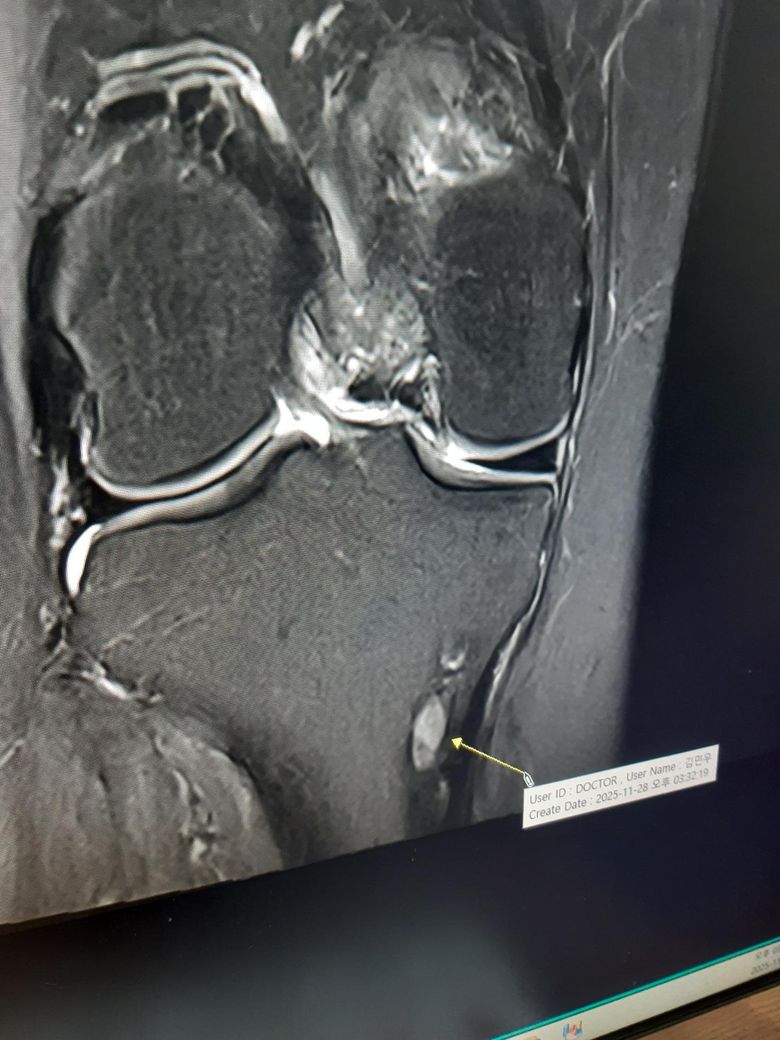

무릎mri에 나타나는 정강뼈에 하얀 이것은 뭘까요?

제공하신 MRI 이미지는 해상도가 낮고 단면이 제한적이라 단정적인 판단은 어렵지만, 정강뼈(경골) 안쪽 아래 부위에 국소적으로 보이는 ‘둥근 하얀 구조’는 보통 다음 가능성 중 하나로 해석됩니다.

1. 거위발(안쪽) 주변의 점액낭염 또는 염증 변화

거위발건(봉공근·박근·반건양근) 부위에는 점액낭이 있어 염증이 생기면 MRI에서 밝게(하얗게) 보이는 액체 신호가 나타날 수 있습니다.

위치가 경골 내측 하단(정강뼈 안쪽)이라면 거위발 점액낭염(pes anserine bursitis) 가능성이 있습니다.

2. 경골 내측의 소규모 낭종(ganglion-like cyst) 또는 지방종류(파이브로이드 변화 포함)

관절 주변에서는 소규모 낭종성 병변이 생기는 경우가 있는데, MRI에서 둥근 모양의 고신호로 관찰됩니다.

4. 거위발건염 자체가 직접 MRI에서 ‘하얀 점’처럼 보이진 않음

참고로 거위발건염은 건 자체가 두꺼워지거나 주변 점액낭에 액체가 차는 형태로 보이지,

지금 보이는 것처럼 둥근 독립된 ‘하얀 덩어리’ 형태로 보이는 건 아니기 때문에

점액낭염 또는 낭종성 병변에 더 가깝습니다.

현재 사진만 보면

거위발건염보다는 ‘거위발 점액낭염 또는 작은 낭종성 병변’ 가능성이 더 높습니다.

위험한 병변으로 보이진 않으나, 통증이 있다면 주사 치료, 스트레칭, 보행 패턴 교정 등이 필요할 수 있습니다.

사진 한 장만으로 단정할 수는 없지만, 표시된 부위가 무릎 안쪽 하방이라면 "거위발건염/거위발" 점액낭염 위치와는 어느 정도 맞아 보입니다.

다만 MRI에서 밝게 보이는 병변은 "점액낭염, 국소 부종, 작은 낭종" 등도 감별이 필요합니다.